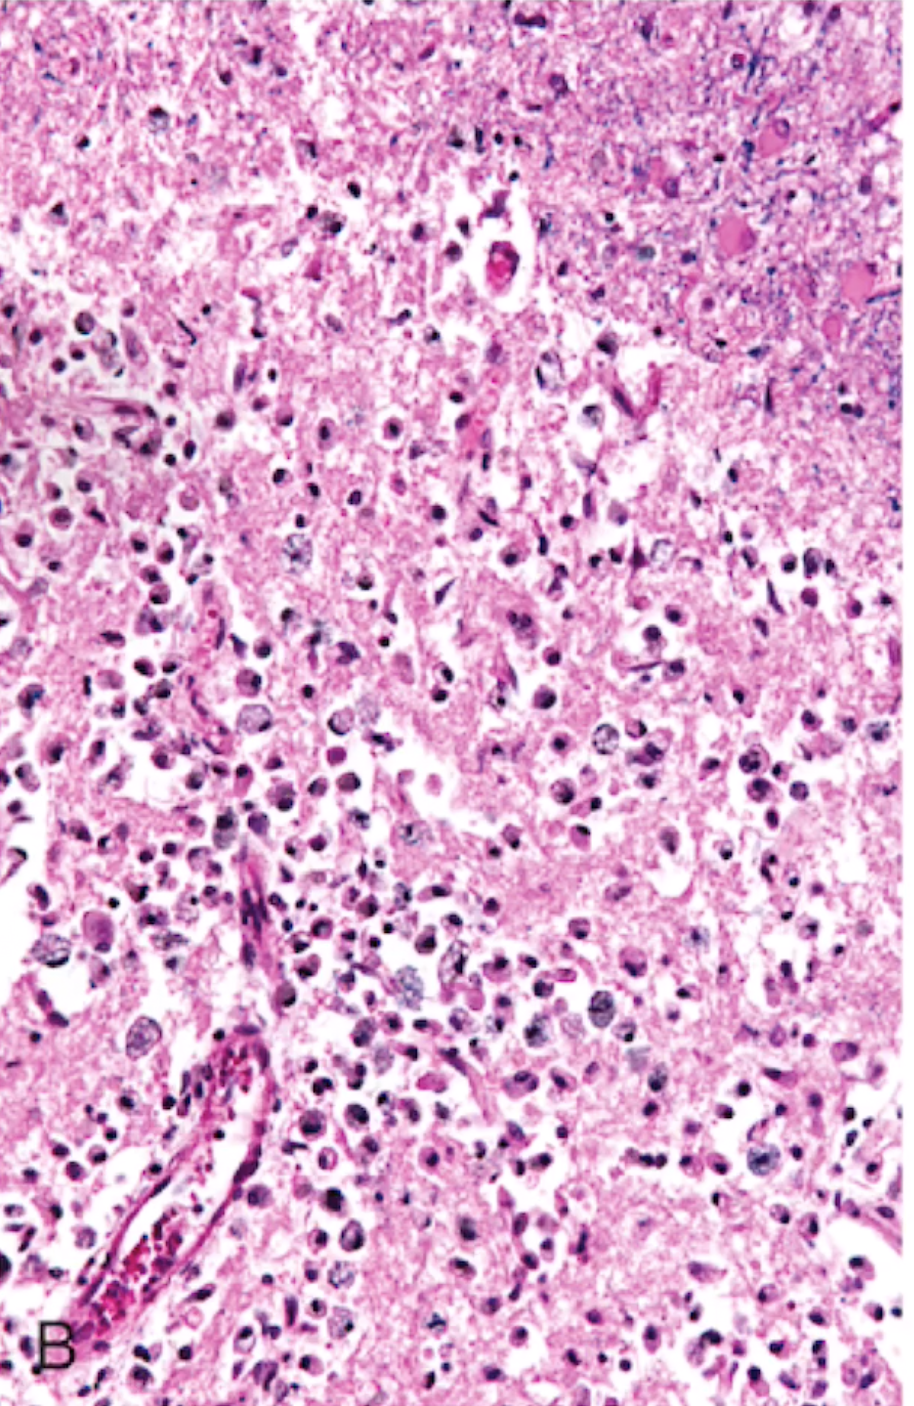

Focal Cerebral Ischemia